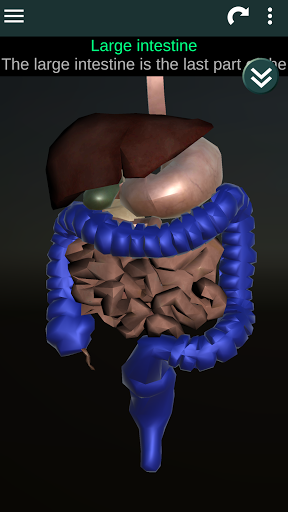

Shows a 3D anatomical model of the main organs of the human body and a description of each one.

* Digestive system, including the stomach, small intestine, large intestine, and an animation of this system.

* Easy to access and navigate (zoom, 3D rotation).

* Descriptions of each organ.